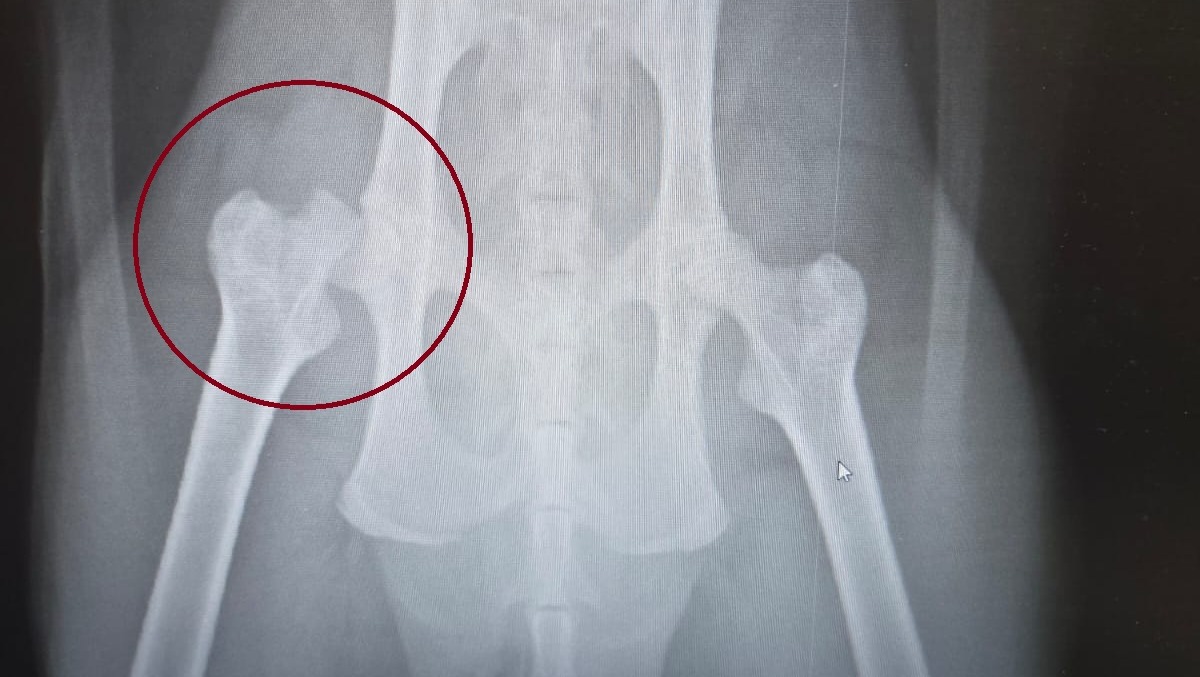

Our cat, Ludo, has recently taken a very serious fall and broke his Femoral Head. Basically the bone that inserts in to his hip. He is scheduled for surgery on Monday. He is a 1.5 year old Maine Coon, full of energy and spunk but this injury has completely immobilized him. Every little bit can help with the medical expenses, medication and after care. And we would appreciate it beyond belief.